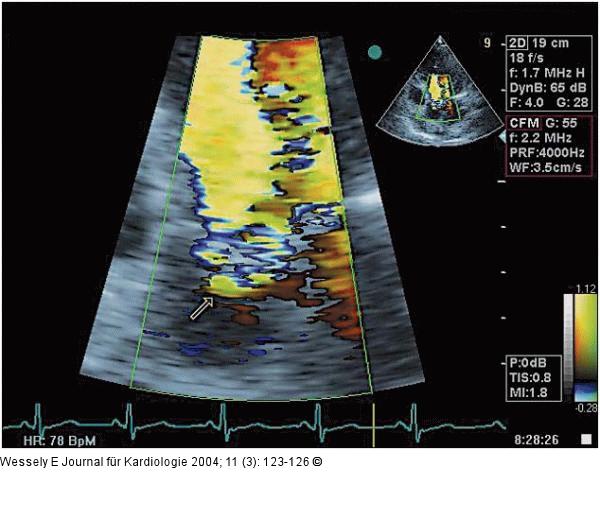

Abbildung 3: Aortenklappeninsuffizienz - Endokarditis Flowkonvergenzzone oberhalb der Aortenklappe, diastolisches Farbdopplersignal im apikalen 5-Kammerblick |

Abbildung 3: Aortenklappeninsuffizienz - Endokarditis

Flowkonvergenzzone oberhalb der Aortenklappe, diastolisches Farbdopplersignal im apikalen 5-Kammerblick |